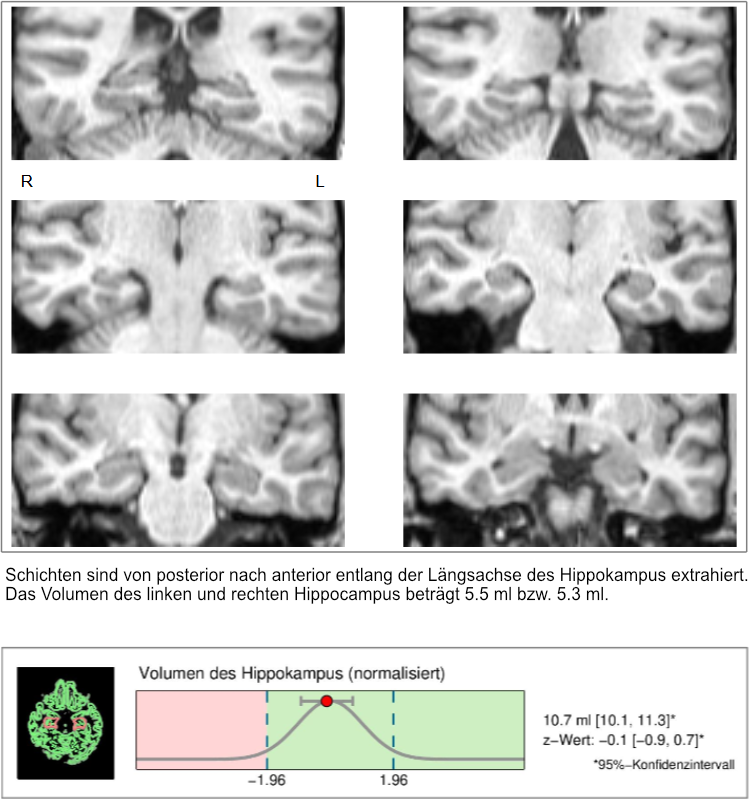

ARDX® is a standardized, low-threshold test that extends conventional dementia screening tests by an evidence-based biomarker methodology (hippocampal volumetry).

Based on structural magnetic resonance imaging (MRI) data of the head, the individual hippocampal volume is determined with the help of a computer-assisted procedure. The MRI examination takes only a few minutes and is performed without the administration of contrast medium.

The hippocampal volumetry has been validated in many scientific studies, and the computer-assisted procedure is certified as a medical device.

Hippocampal volumetry

Result of diagnostic test

If the findings are inconspicuous (normal hippocampal volume), incipient Alzheimer's dementia can be ruled out with a high degree of probability at present (Suppa et al. 2015a) and for the next three years (Suppa et al. 2015b).

In the event of an abnormal finding (reduced hippocampal volume), a supplementary diagnostic assessment should be considered.